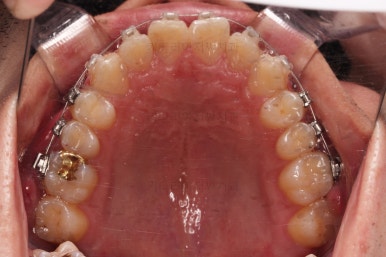

초진 시 입안의 모습입니다.

비교적 고른 편이긴 하나 아랫니가 전반적으로 밀려 나오면서 앞니끼리 부딪혀 있는 양상이고요.

어금니 맞물림도 긴밀하게 톱니바퀴처럼 위아래가 맞물려 있는게 아니라 엉성한 모습이죠.

앵글씨 3급 부정교합이라고 하는데요.